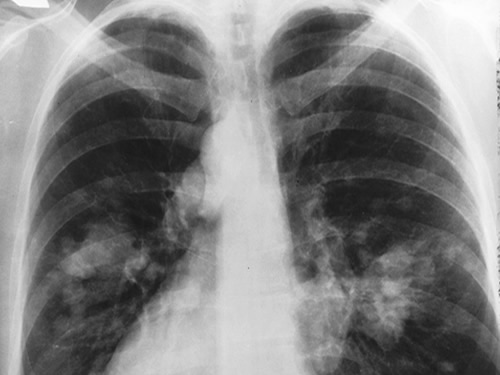

Um exame de sangue em estudo aumenta a precisão de detecção precoce do câncer de pulmão, diz a Organização Mundial de Saúde. O teste identifica cinco proteínas específicas, chamadas de "biomarcadores", que podem ser encontradas antes da formação dos tumores.

Uma detecção se faz urgente, afirma o estudo, porque o rastreamento atual de câncer de pulmão não diagnostica uma grande fração dos tumores.

Enquanto o teste fez a previsão de 63% de futuros pacientes com câncer, a tomografia conseguiu prever o câncer de pulmão em 42% dos pacientes.

O estudo também foi publicado no "JAMA Oncology" e mostrou que o teste foi capaz de prever com mais precisão que tomografia cânceres em estágio inicial.